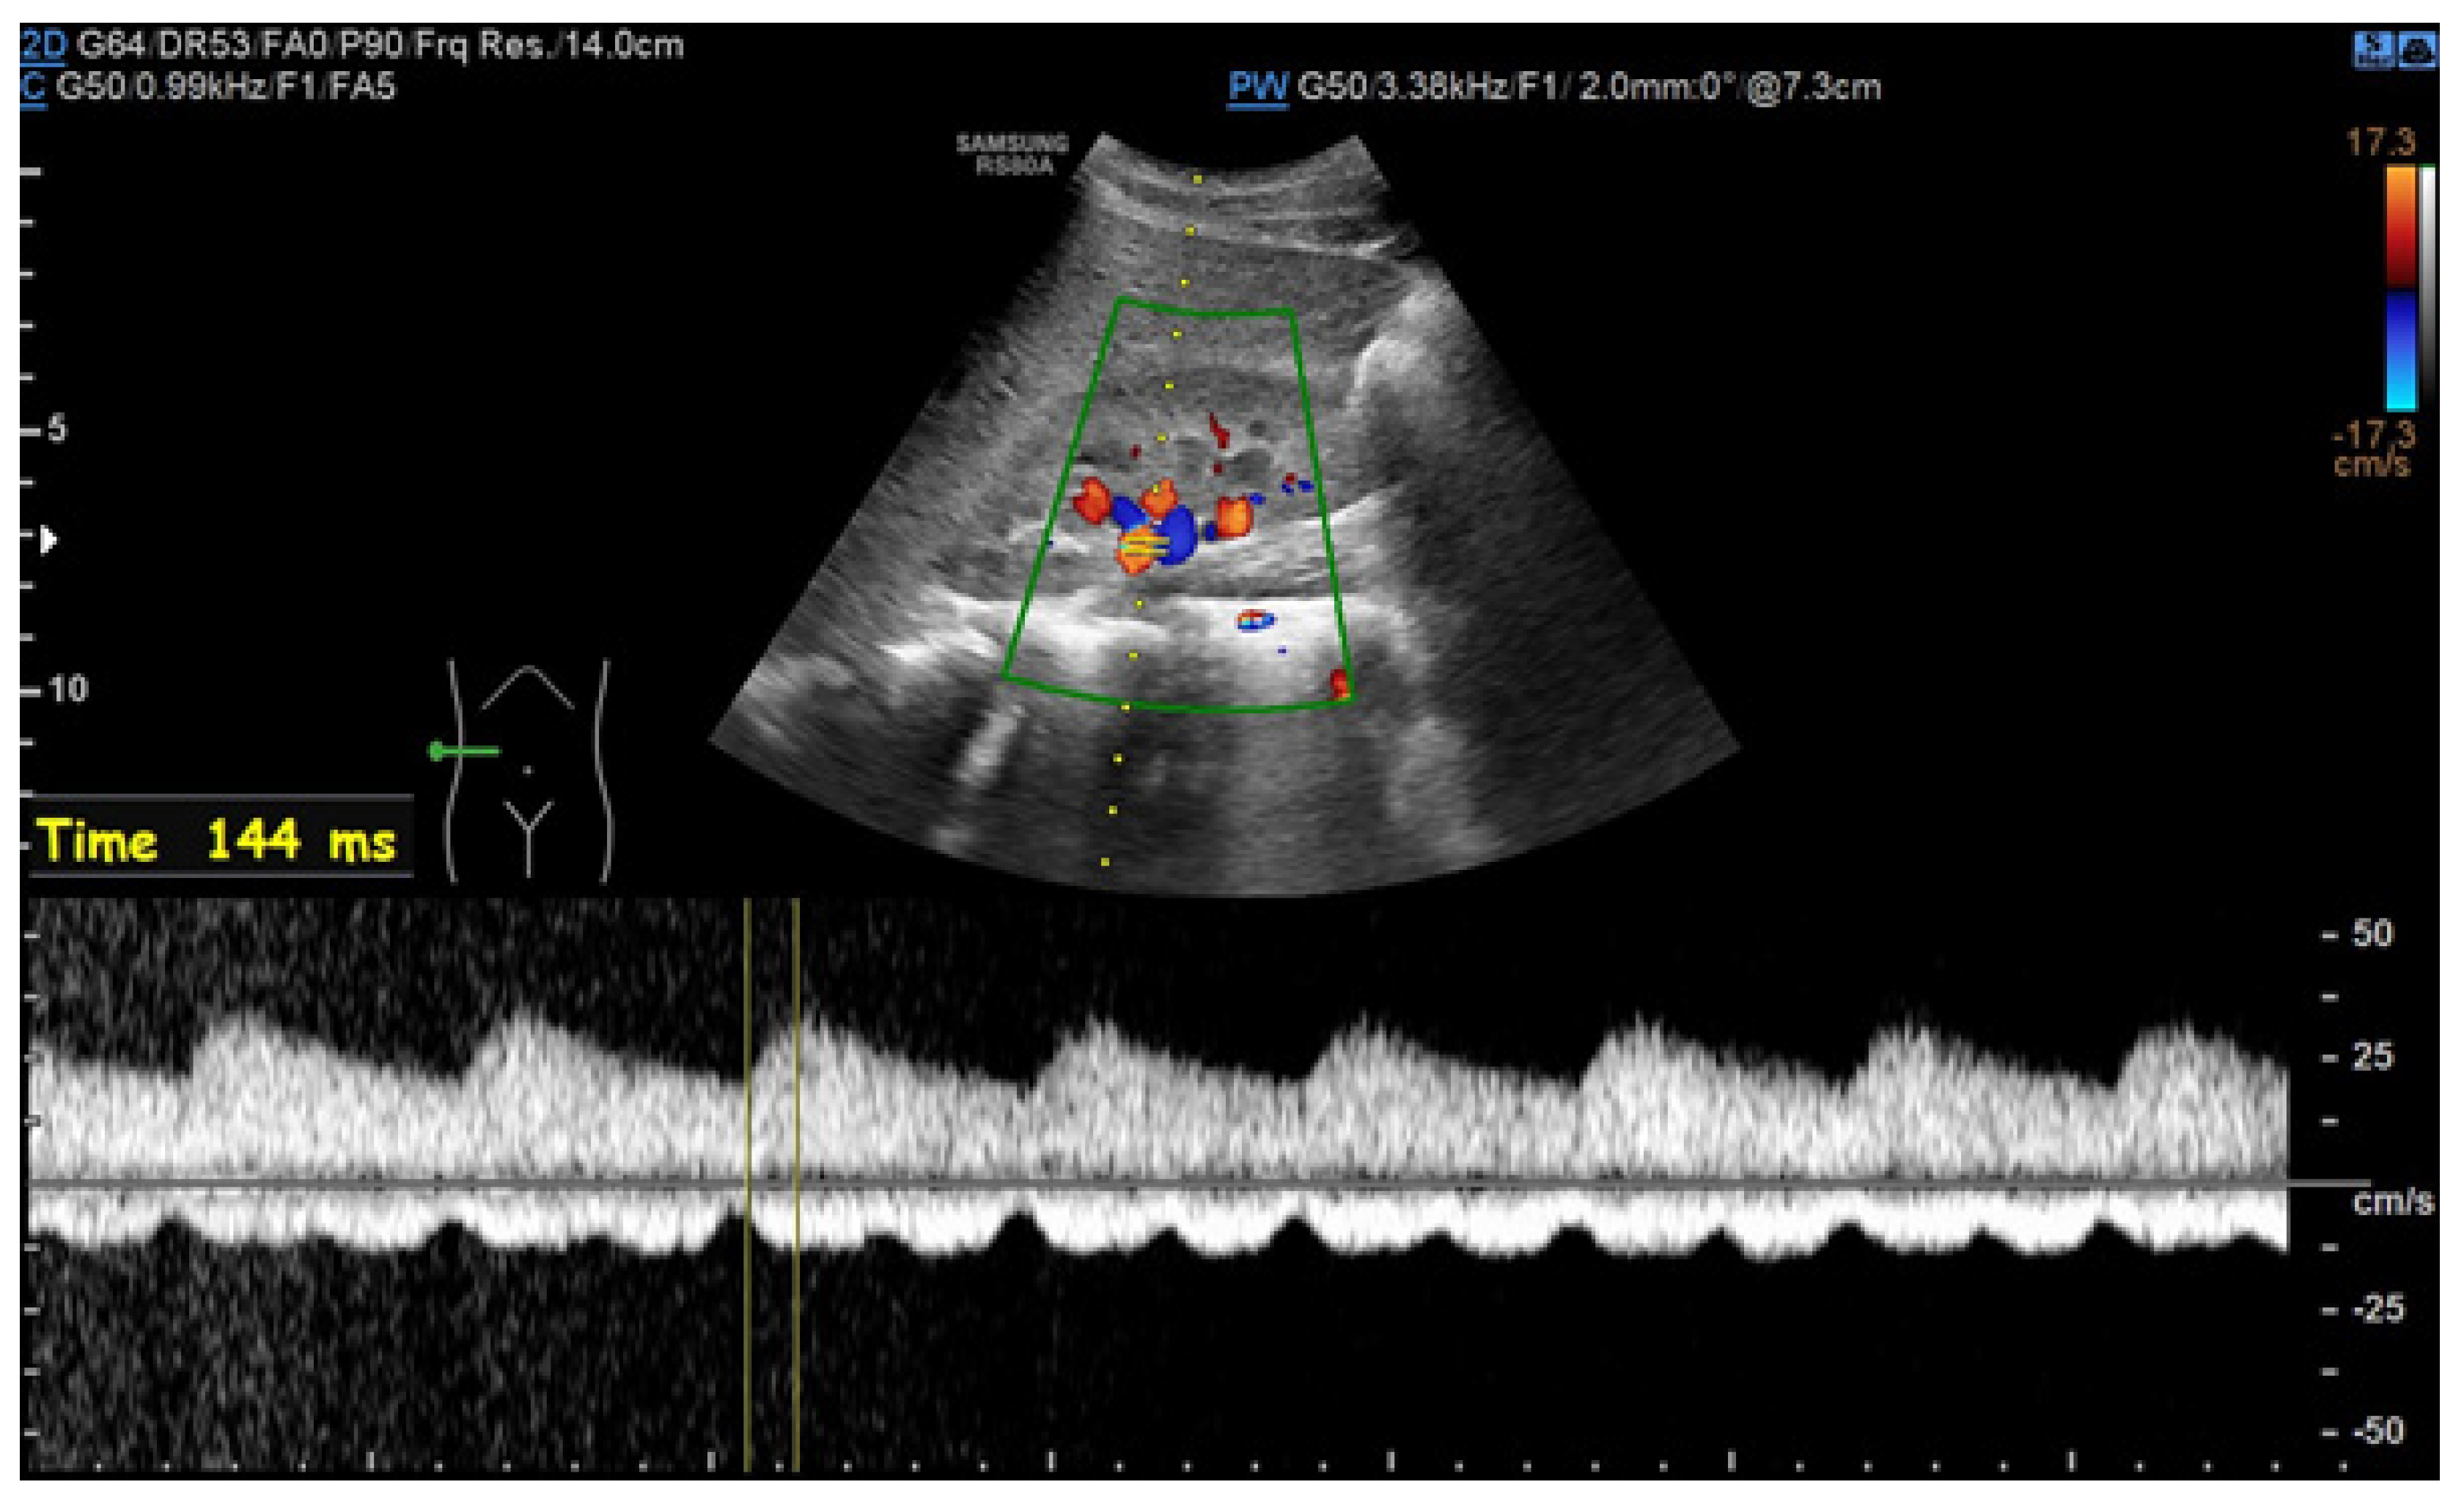

6.1. Ultrasound

- Drelich-Zbroja, A. Polish Society of Ultrasonography Standards—Update: Ultrasound Examination of Renal Arteries. J. Ultrason. 2014, 14, 297–305. [Google Scholar] [CrossRef]

- Stryczyński, Ł. Doppler ultrasound of renal arteries. Arter. Hypertens. Pract. 2022, 8, 186–199. [Google Scholar]

- Saida, K.; Kamei, K.; Hamada, R.; Yoshikawa, T.; Kano, Y.; Nagata, H.; Sato, M.; Ogura, M.; Harada, R.; Hataya, H.; et al. A simple, refined approach to diagnosing renovascular hypertension in children: A 10-year study. Pediatr. Int. 2020, 62, 937–943. [Google Scholar] [CrossRef]

| Normal Value | Parameter |

|---|---|

| 100 cm/s * | PSV (peak systolic velocity) in artery trunk |

| 0.8–1.0 | RAR (renal aortic ratio) in artery trunk |

| ≤70 ms | AT (acceleration time) in intrarenal branches |

| 0.5–0.8 | RI (resistance index) in intrarenal branches |

| 0.78–1.33 | PI (pulsatility index) in intrarenal branches |

| >3 m/s2 | AI (acceleration index) in intrarenal branches |